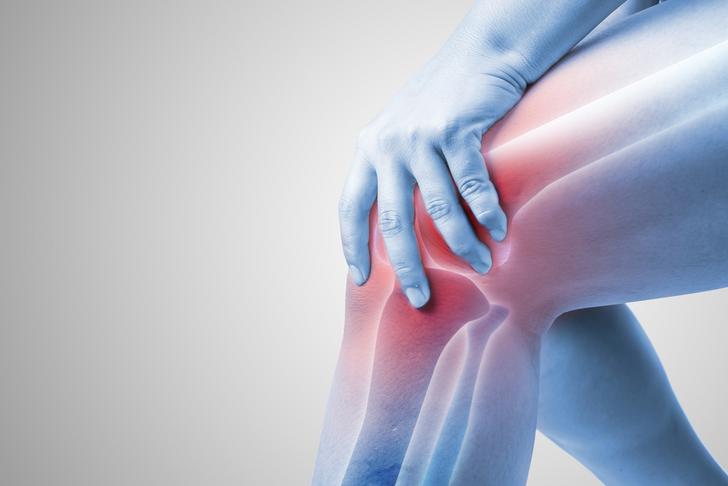

Joint Pain

Joint pain is one of the most common symptoms of rheumatoid arthritis. It is usually a result of inflammation in the joint lining, which can cause swelling, warmth, and tenderness[[1]]. Pain is often worse in the morning or after periods of inactivity.

Joint Swelling

Swelling is another common symptom of RA, as the inflamed joint lining produces excess fluid. This can lead to visibly swollen and tender joints, particularly in the hands, wrists, and knees[[2]].

Joint Stiffness

Stiffness in the joints is a common complaint among those with rheumatoid arthritis. It is often most noticeable in the morning or after periods of inactivity, and can last for several hours[[1]].

Joint Deformity

Over time, the inflammation caused by rheumatoid arthritis can damage the joints and surrounding tissues, leading to joint deformity. This can result in a loss of function and mobility, as well as changes in the appearance of the affected joints[[1]].